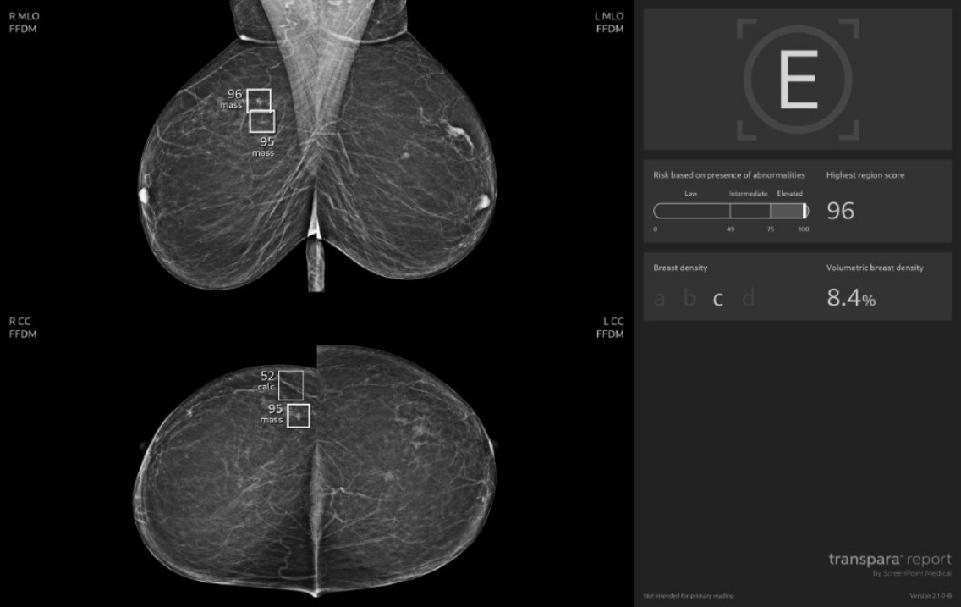

OZP je také první českou zdravotní pojišťovnou, která v preventivních programech využívá umělou inteligenci. Od 1. dubna 2023 plně hradí tzv. třetí čtení mamografických snímků. Odborným garantem tohoto projektu je prof. MUDr. Jan Daneš, CSc., předseda Komise pro screening karcinomu prsu. Podle něj se díky AI zvýšila citlivost screeningu až o 20 procent.

„Od ledna 2024 do srpna 2025 využilo možnost mamografického vyšetření s přispěním umělé inteligence 6397 našich klientek. Na základě nálezu pomocí AI absolvovalo 49 našich pojištěnek biopsii a u 34 z nich se potvrdil maligní nález. Využívání umělé inteligence nejen v rámci prevence tedy podle nás rozhodně dává smysl, zvyšuje celkovou senzitivitu vyšetření a snižuje počet zbytečných doplňujících vyšetření,“ komentuje dosavadní výsledky zdravotní ředitelka OZP MUDr. Jitka Vojtová, MBA.